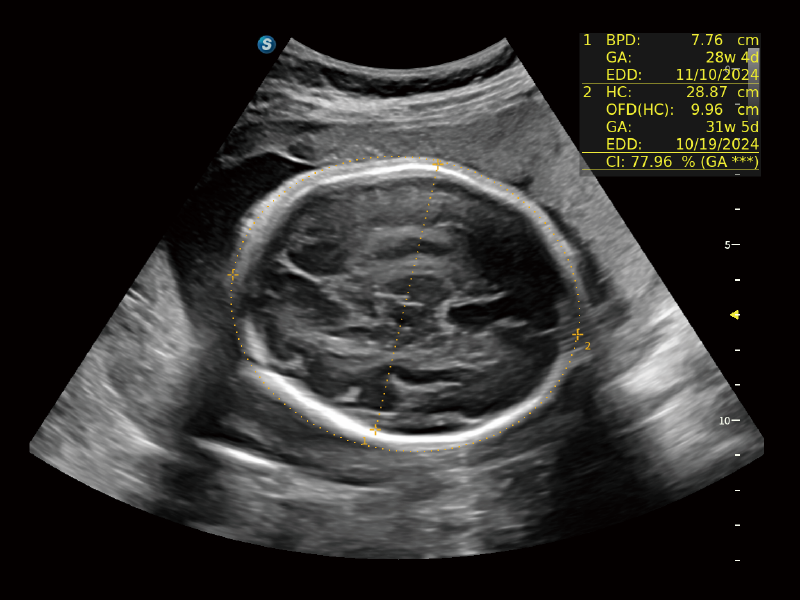

作为开立医疗全新打造的超高端旗舰超声产品,从探头抬起唤醒开启扫查到多维探头发射接收,通过先进的场成像发射、自适应聚合重建等技术,基于RF Data原始射频数据在图像生成、高端功能等方面实现突破,为妇产科、儿科提供全方位临床解决方案。

独有场成像发射技术

自适应聚合重建技术

独家XPUs混合硬件架构